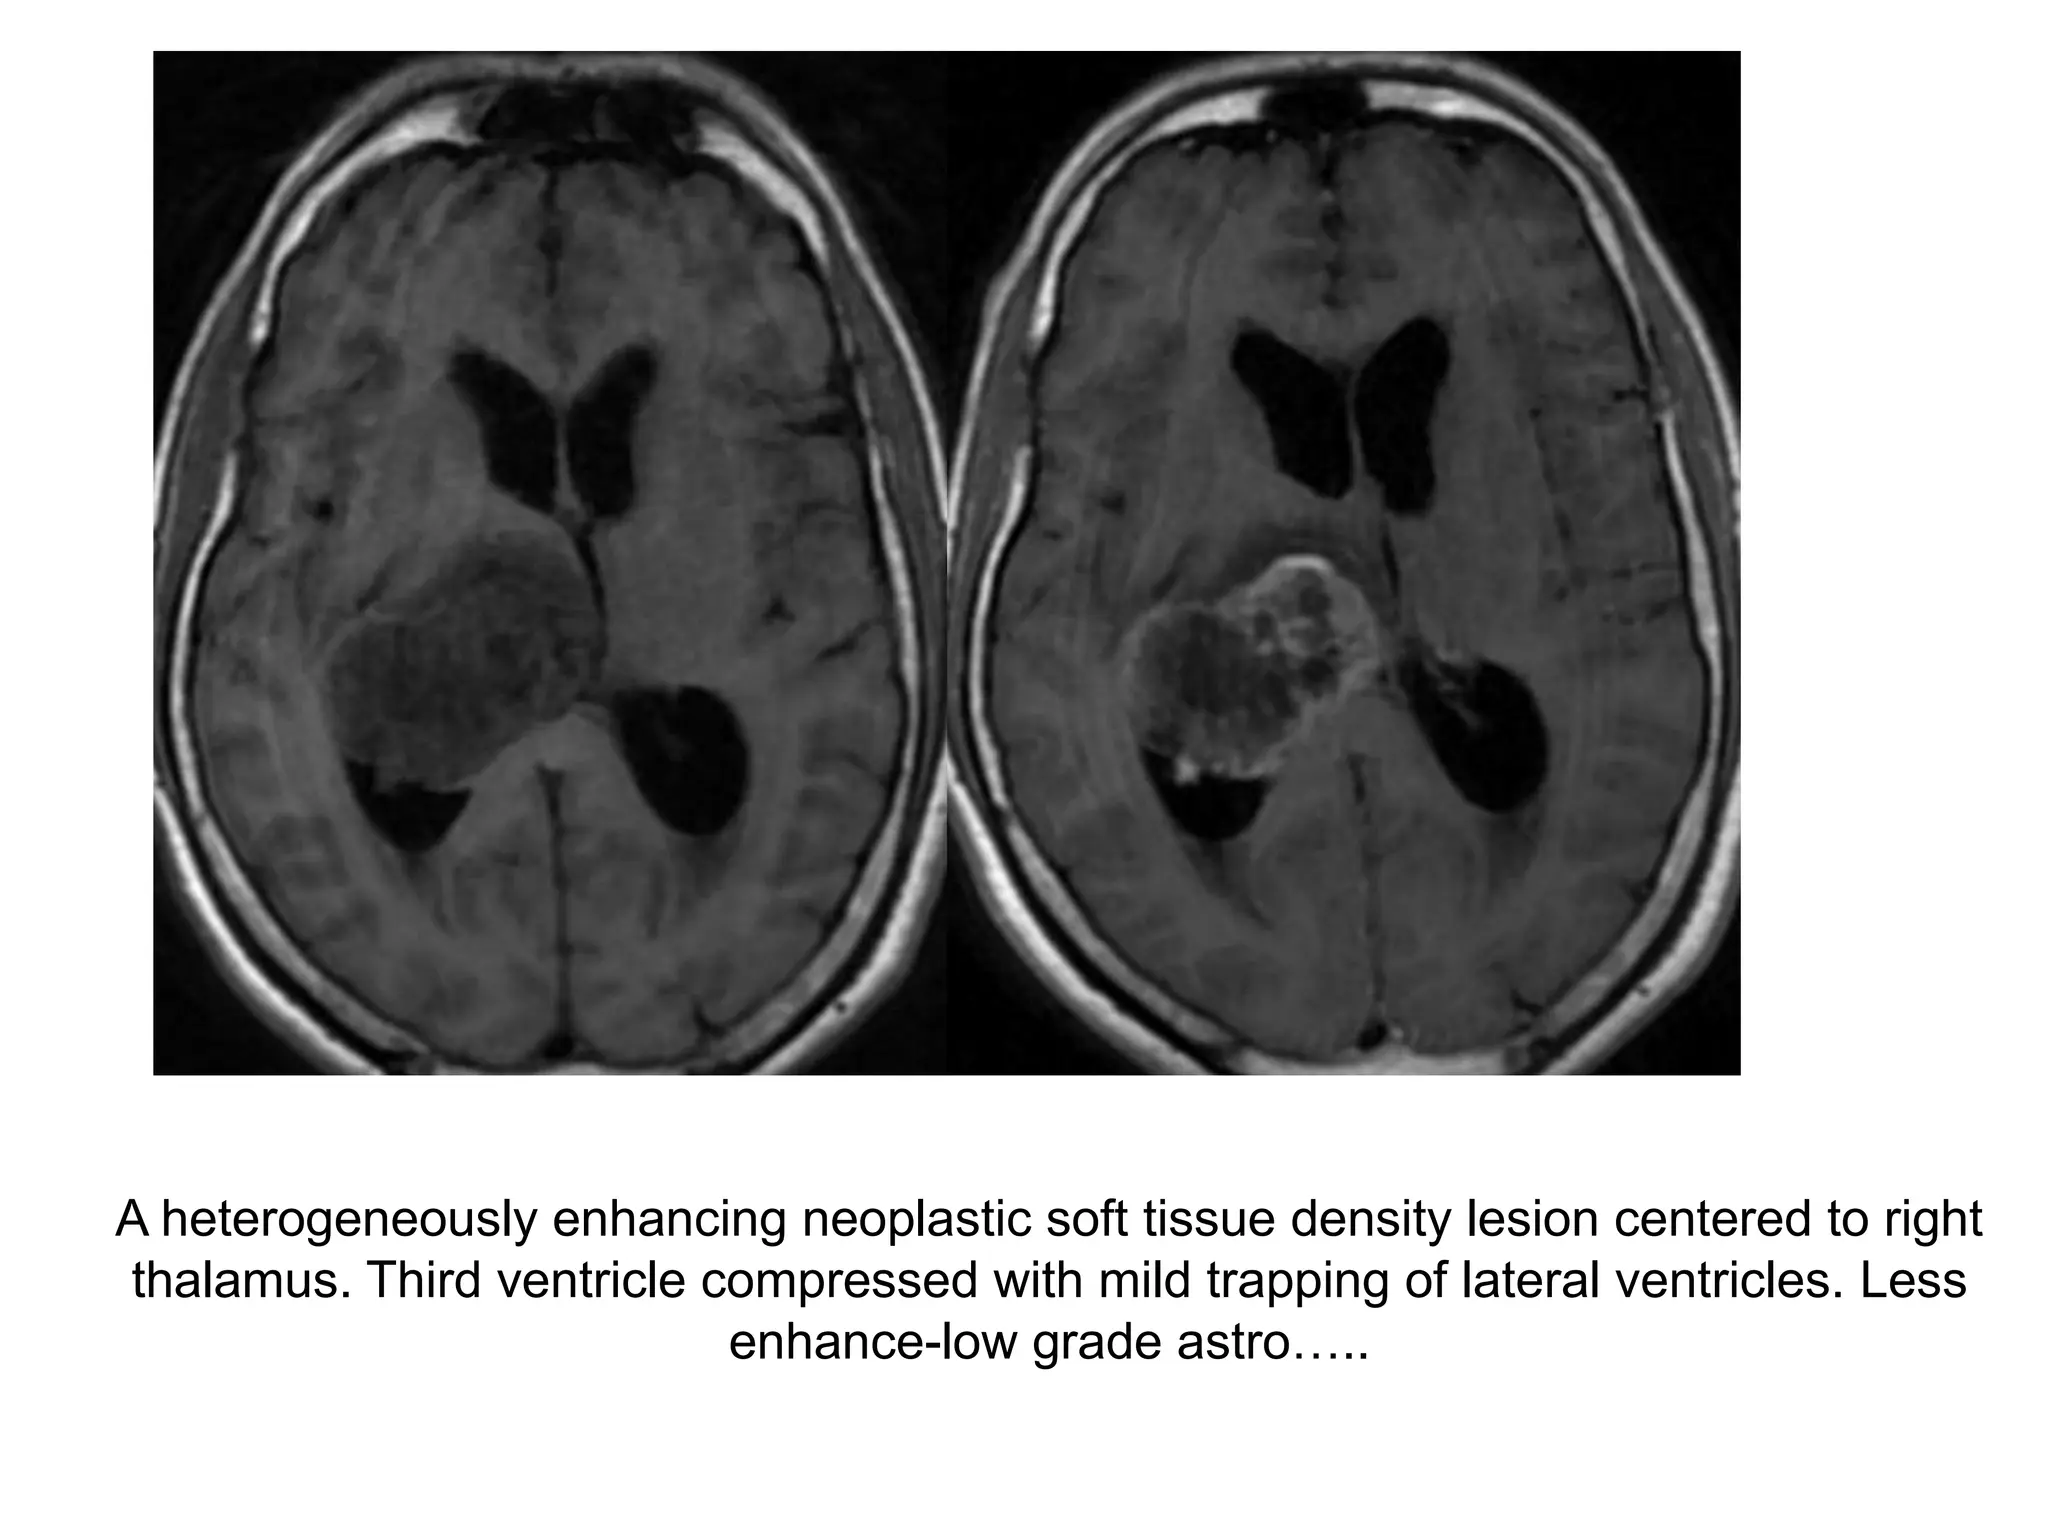

A heterogeneously enhancing neoplastic soft tissue density lesion centered to right

thalamus. Third ventricle compressed with mild trapping of lateral ventricles. Less

enhance-low grade astro…..